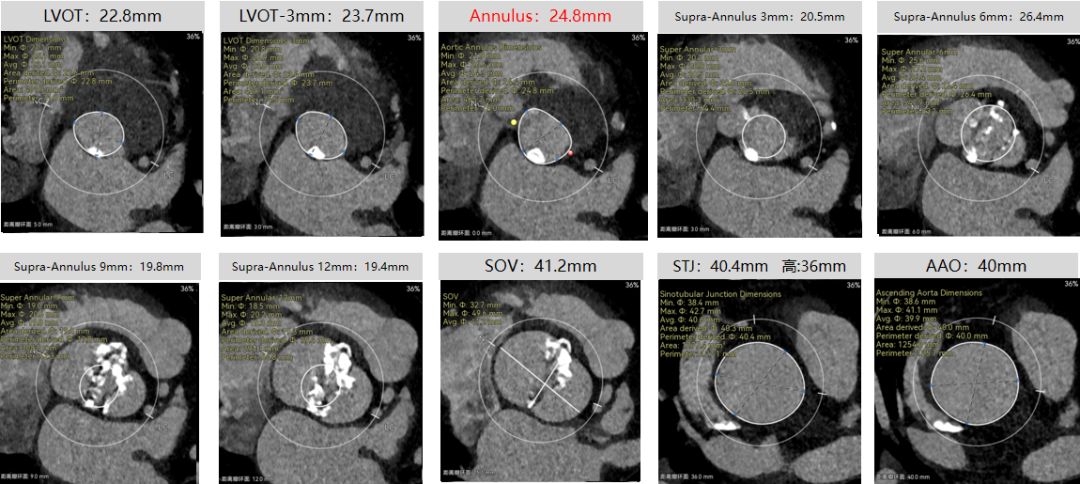

彭小平教授 南昌大学第一附属医院 不断探索医疗可能,筑牢患者长期保障 TAVR 治疗的终极目标,不仅是完成一次手术,更是为患者构建长期稳定的生命保障,而瓣膜耐久性是直接关乎患者后期是否需要二次手术的关键所在。全球首款预装干瓣的问世,为临床提供了全新的选择方案。厂家的15 年质保承诺,是源于材料研发的突破与临床验证的底气。从临床角度,如未来瓣膜可以耐久15年,则可大大减少患者反复就医的身心负担与经济压力,本质上是为患者的长期健康 “投保”。 人生的每一次选择,都需要慎重。相信在行业的前行中,我们不断探索医疗的可能性,让每一次治疗都能真正护航患者长远健康! 患者病史 主诉与现病史:3 年前开始出现胸闷、气促,活动后(如上楼、上坡)症状加重,休息后可缓解,当地医院心脏彩超提示主动脉瓣狭窄,未予特殊治疗;2 年前发现血压轻度升高,口服阿奇沙坦片(40mg,每日 1 次)降压,血压控制尚可;近 1 个月胸闷气促症状明显加重,2025 年 10 月 13 日外院心脏彩超提示主动脉瓣重度狭窄,为进一步诊治入院。 既往史:高血压病史 2 年,规律服用阿奇沙坦片(40mg qd);1 年余前因外伤致腰椎骨折,保守治疗后痊愈;有慢性阻塞性肺疾病病史;有胃窦糜烂、十二指肠球部溃疡史,2023 年曾发生急性上消化道出血;有真菌性食管炎、多发性结肠息肉病史。 术前超声提示:主动脉瓣钙化,主动脉瓣狭窄(重度),左室肥厚,升主动脉增宽。 二尖瓣反流(轻度),三尖瓣反流(轻度),肺动脉瓣高压(轻度)。 左室舒张功能减低,收缩功能正常,左室射血分数 74.7%。 术前CT:Type0型二叶瓣,瓣叶增厚并极重度钙化,钙化主要分布在瓣叶基底部,延伸到左室流出道。主动脉瓣环径24.8mm;升主动脉狭窄后扩张至主动脉弓,双侧瓣叶开口高度可,窦部空间可,STJ内径增宽,升主动脉内径可,预估冠脉低风险;主动脉水平夹角49.1°,非横位心;主动脉弓角、弓距可;“自杀左室”,建议术前补液,ECMO湿备,术中注意循环崩溃。 外周双侧入路内径可,髂总动脉有零星散状钙化,双侧股动脉均能通过20F大鞘,右股低分叉。 手术策略:推荐使用右侧股动脉为主入路,左侧股动脉为辅助入路;右股分叉上方1cm穿刺;推荐使用18mm球囊预扩,预装AV23瓣膜。 手术过程:在右股动脉穿刺建立通路后,顺利送入大鞘,经食道超声及血管造影确认路径稳定。18mm球囊预扩后评估冠脉灌注良好,后将Prostyle A® AV23瓣膜精准释放于目标位置,20mm球囊后扩,超声显示轻微瓣周漏,术后即刻造影显示无明显反流,峰值压差由术前的80mmHg降至12mmHg,心功能明显改善,患者生命体征平稳。 18球囊预扩无腰无漏 输送器跨瓣顺利 定位 平稳释放瓣膜 20球囊后扩 最终造影,位置良好,轻微瓣周漏 Prostyle A®预装干瓣——助力临床最优化解决方案 1、流入端桶状设计:流入端桶状的设计,锚定迅速,有效减少释放步骤,提升植入稳定性; 2、平衡的收腰设计:二叶瓣小心室患者对瓣膜径向支撑力提出更高要求,Prostyle A®均衡的收腰设计可更好适应小瓣环及不规则瓣口结构,保证了EOA,有效降低了循环崩溃风险,提高瓣膜的耐久性; 3、预装干瓣 便捷顺安:金仕生物专利抗钙化技术运用纳米技术去除组织内的细胞碎片和磷脂,封闭游离醛基,从根本上阻断了瓣膜钙化的多项因素,显著提升了瓣膜的耐久性;同时,相比较传统戊二醛保存方式,干式存储最大限度的保留心包的亲水亲油平衡,还原组织天然曲柔性,进一步保障了瓣叶开合,保证长期耐久性; 专家简介 彭小平 南昌大学第一附属医院(点击查看专家详细简历) · END ·